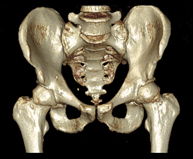

- Pelvic bone CT

Radiological examination based on an X-ray system and detectors that rotate around the patient, reconstructing the images by computer (multidetector computed tomography - MDCT) to study the bones, muscles and joints of the pelvis.